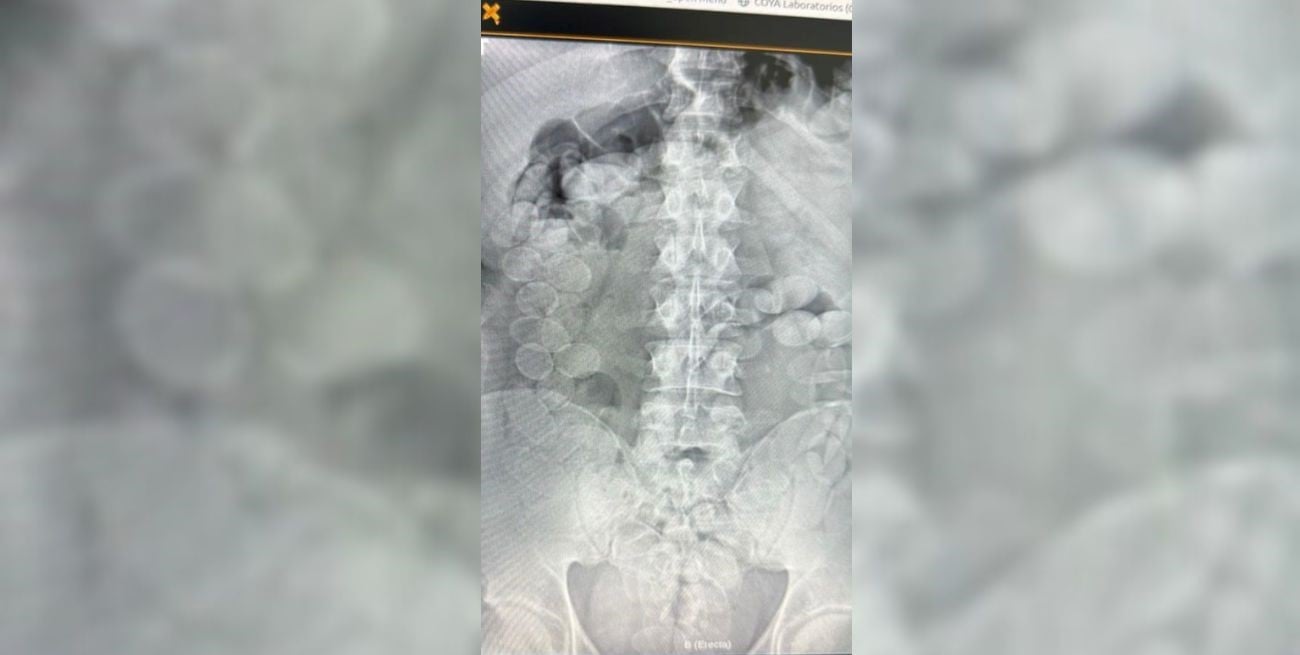

El viaje nocturno de un micro de tour de compras terminó convertido en una escena de emergencia que desbarató un intento de tráfico de cocaína en plena Ruta Nacional 34, en jurisdicción de Ceres. Todo comenzó cuando dos pasajeros bolivianos, que habían abordado la unidad en Orán rumbo a Buenos Aires, empezaron a mostrar señales de un malestar que pronto revelaría su verdadera causa.